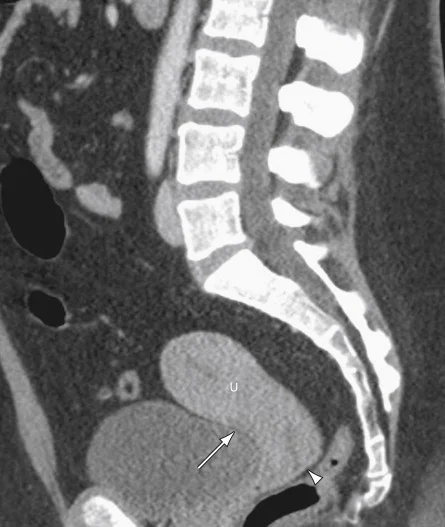

CT Scan

- The diagnostic quality of pelvic scans is improved with use of oral & IV contrast.

- Oral contrast media is used to differentiate between the bowel and adjacent structures.

- IV contrast media used for bloc mass & lymph nodes.

- The fallopian tubes & ovaries

appropriate for detection of

- ovarian tumors

- less appropriate for examination of uterus